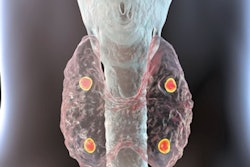

F-18 fluorocholine uptake in parathyroid adenomas in a study participant. Image courtesy of Daniel Thompson.FCH-PET has a high sensitivity and CLR for parathyroid tumors in patients with primary hyperparathyroidism, Thompson concluded. In a subcomparison of FCH and sestamibi, FCH increased the CLR from 7% to 75%, he added.